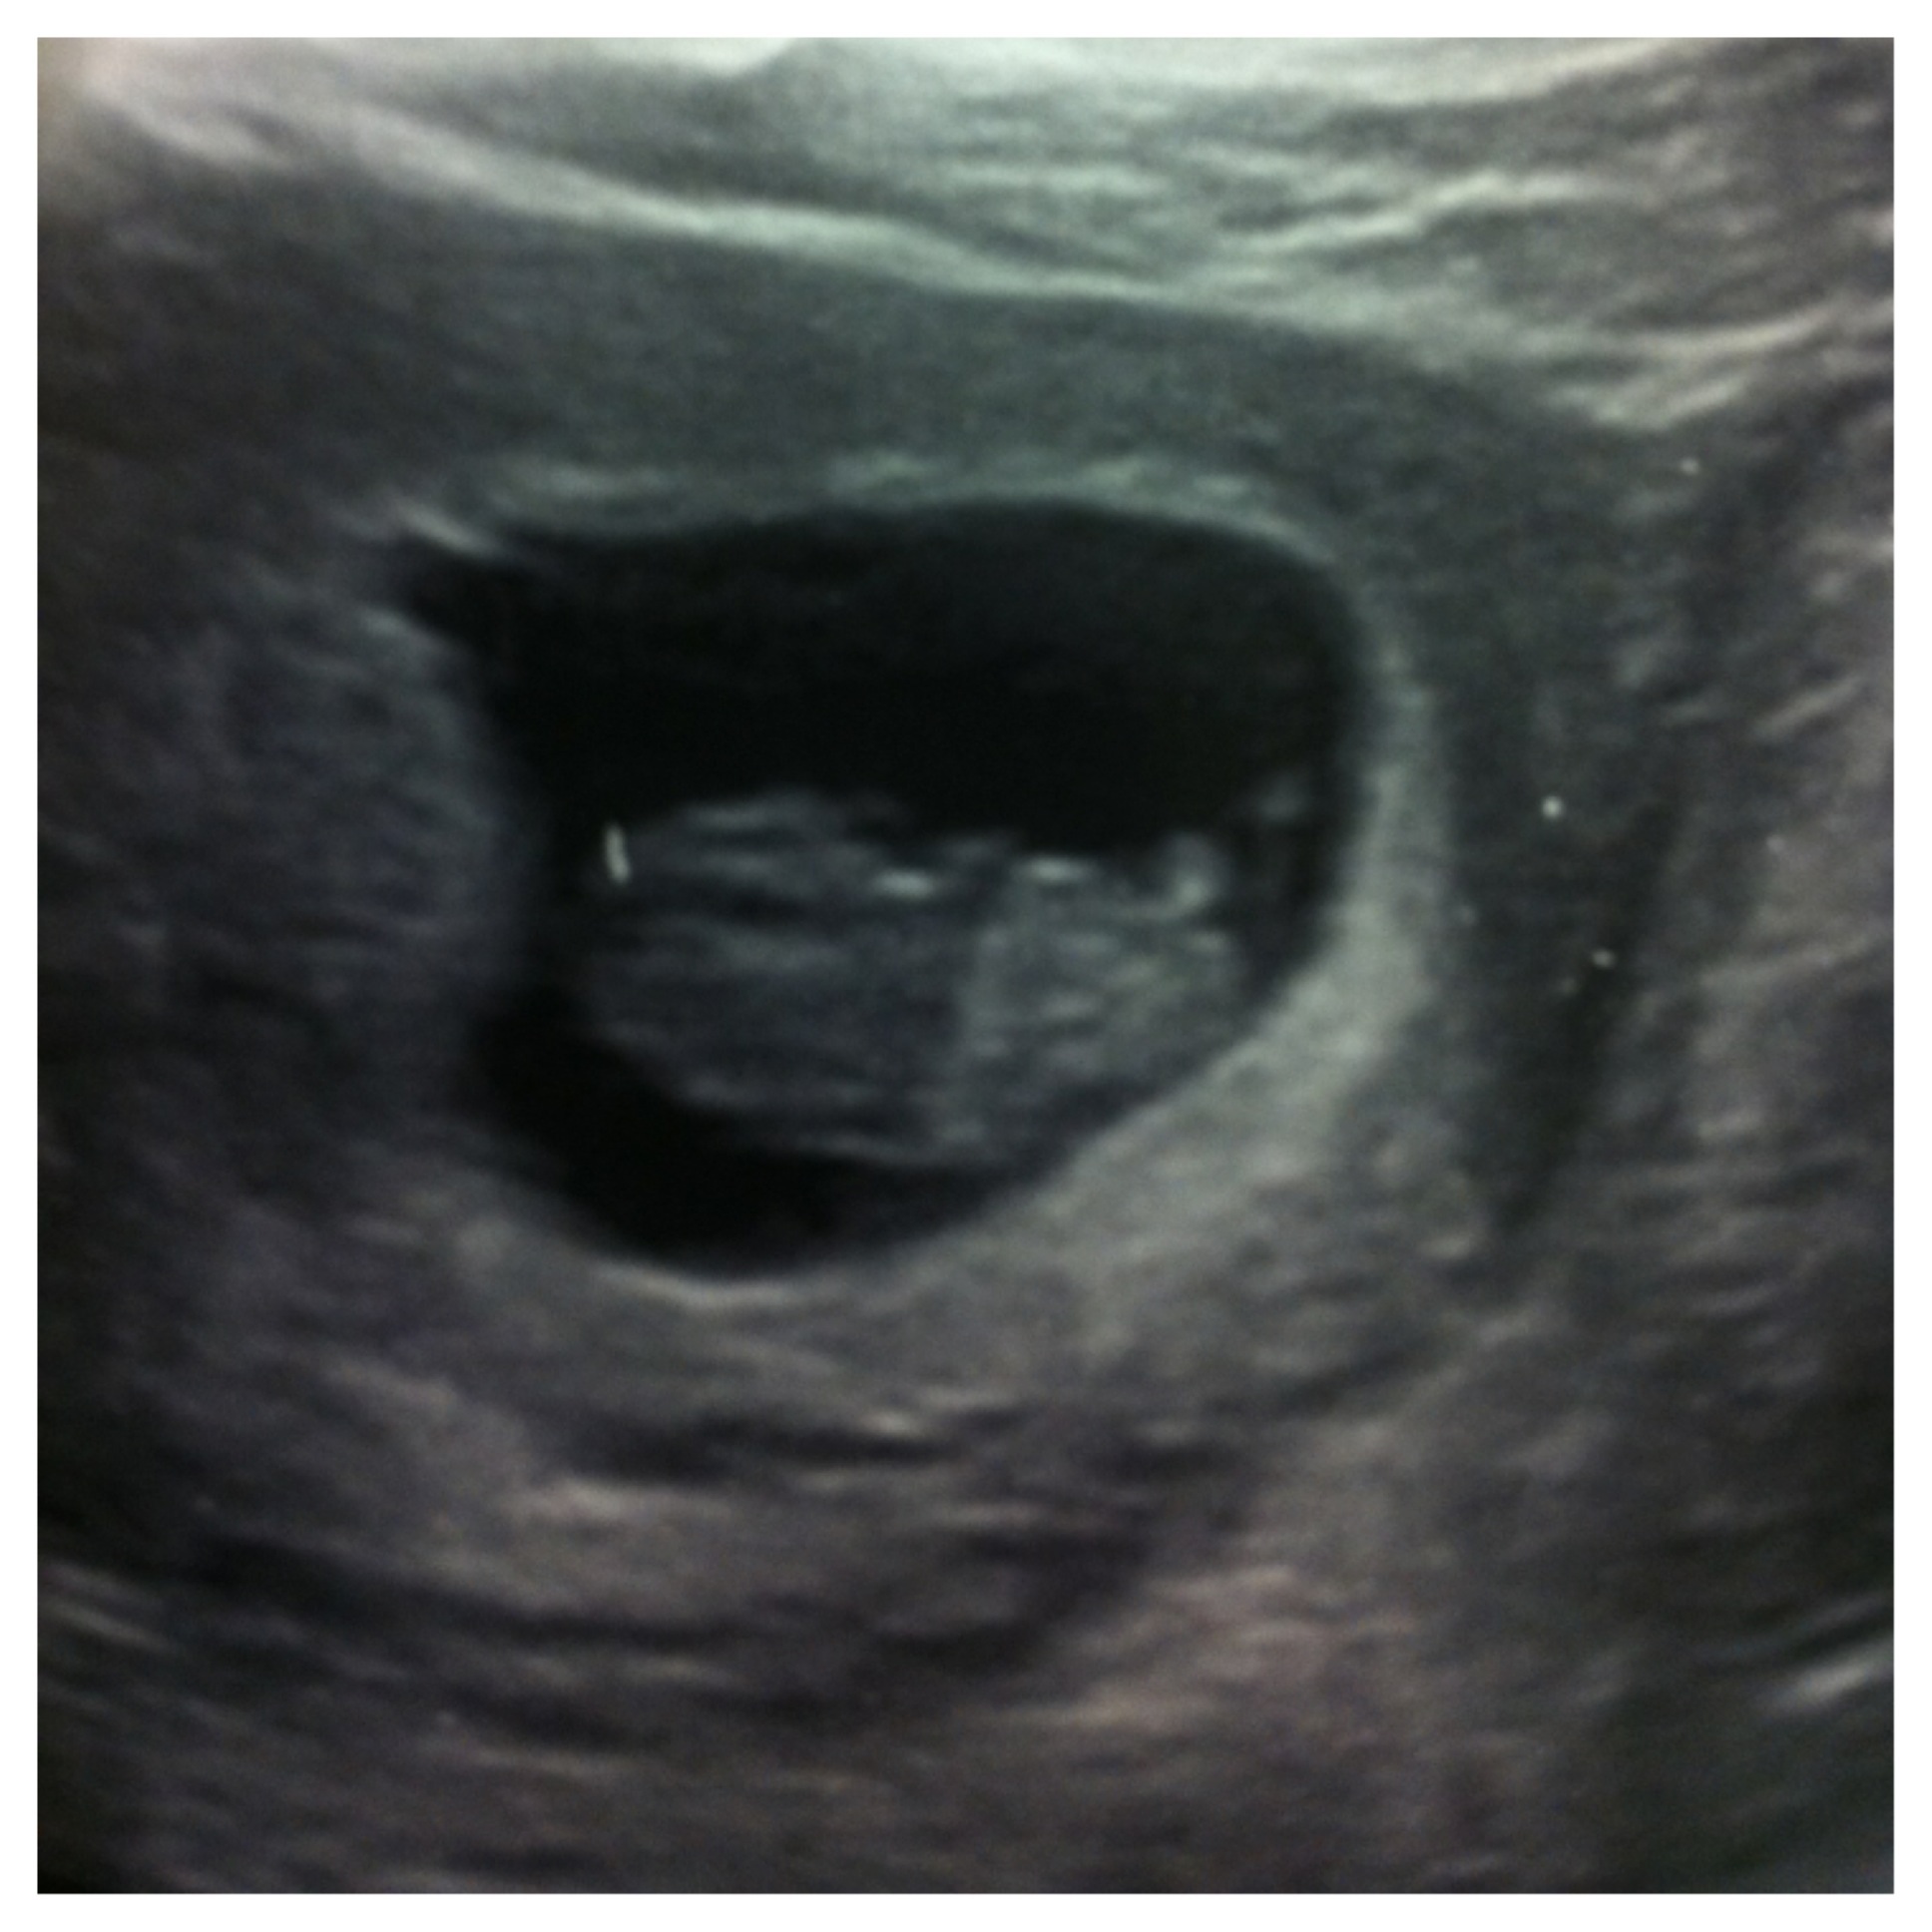

Attachment 13734